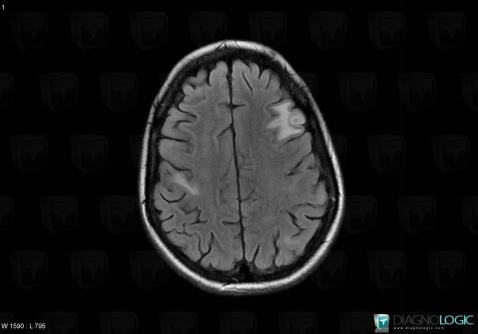

Toxoplasmosis, Cerebral hemispheres, MRI

Here is the specific information in the key image above:

- Diagnosis Toxoplasmosis (link to Abscess), Location(s) Cerebral hemispheres, with gamuts Intracerebral T2W or FLAIR hypointense lesion, Multifocal intracranial lesions